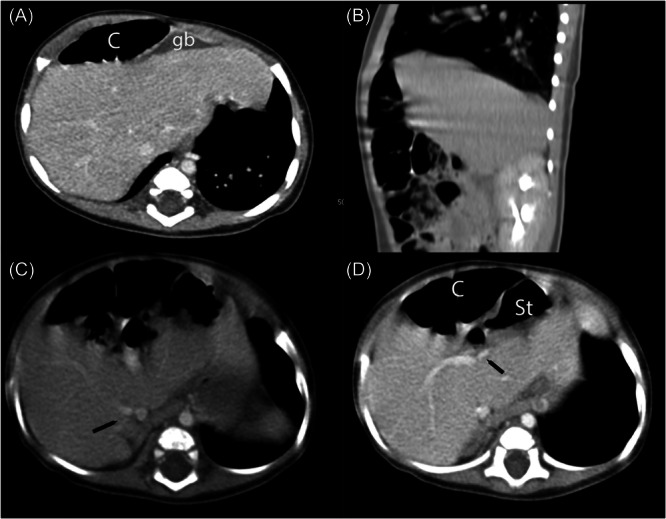

Congenital hepatic anomalies may be associated with important intestinal abnormalities, vascular anomalies, or may be asymptomatic and discovered incidentally. Uncommon and rare anatomic liver and biliary disorders include left-sided gallbladder, wandering liver, malrotation of the liver, and hepato-diaphragmatic interposition of the bowel (Chilaiditi syndrome). This report describes an infant with incidentally discovered malpositioning of the gallbladder to the superior surface of the left hepatic lobe, coupled with Chilaiditi syndrome, a configuration that has not been described in the literature. Management considerations are discussed.